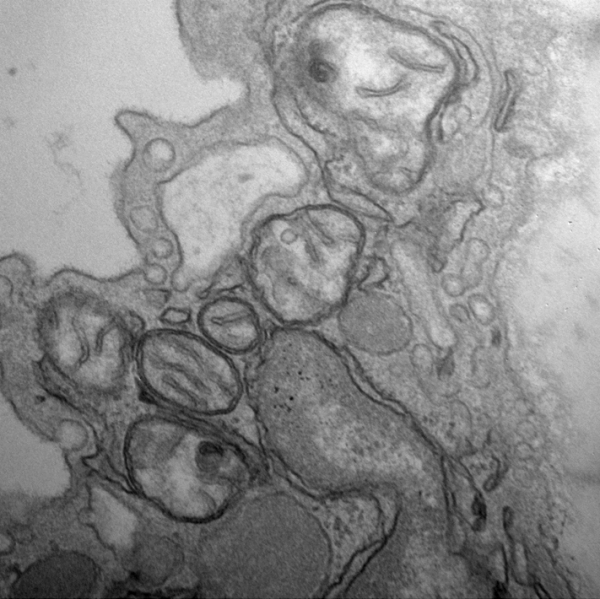

Endothelial mitochondria in mouse aorta were visualized by transmission electron microscopy.

The vast majority of cells in the human body contain tiny power plants known as mitochondria that generate much of the energy cells use for day-to-day activities. Like a dynamic renewable resource, these little power plants are constantly dividing and uniting in processes called fission and fusion. The balance between fission and fusion is critical for health – especially cardiovascular health.

In endothelial cells, chronic inflammation causes mitochondria to become smaller and fragmented. This damaging process is mediated by a molecule known as dynamin-related protein 1 (Drp1). Normally, Drp1 plays a helpful role in maintaining fission-fusion balance. When cells are stressed by inflammation, however, it steps up fission activity, resulting in mitochondrial fragmentation.